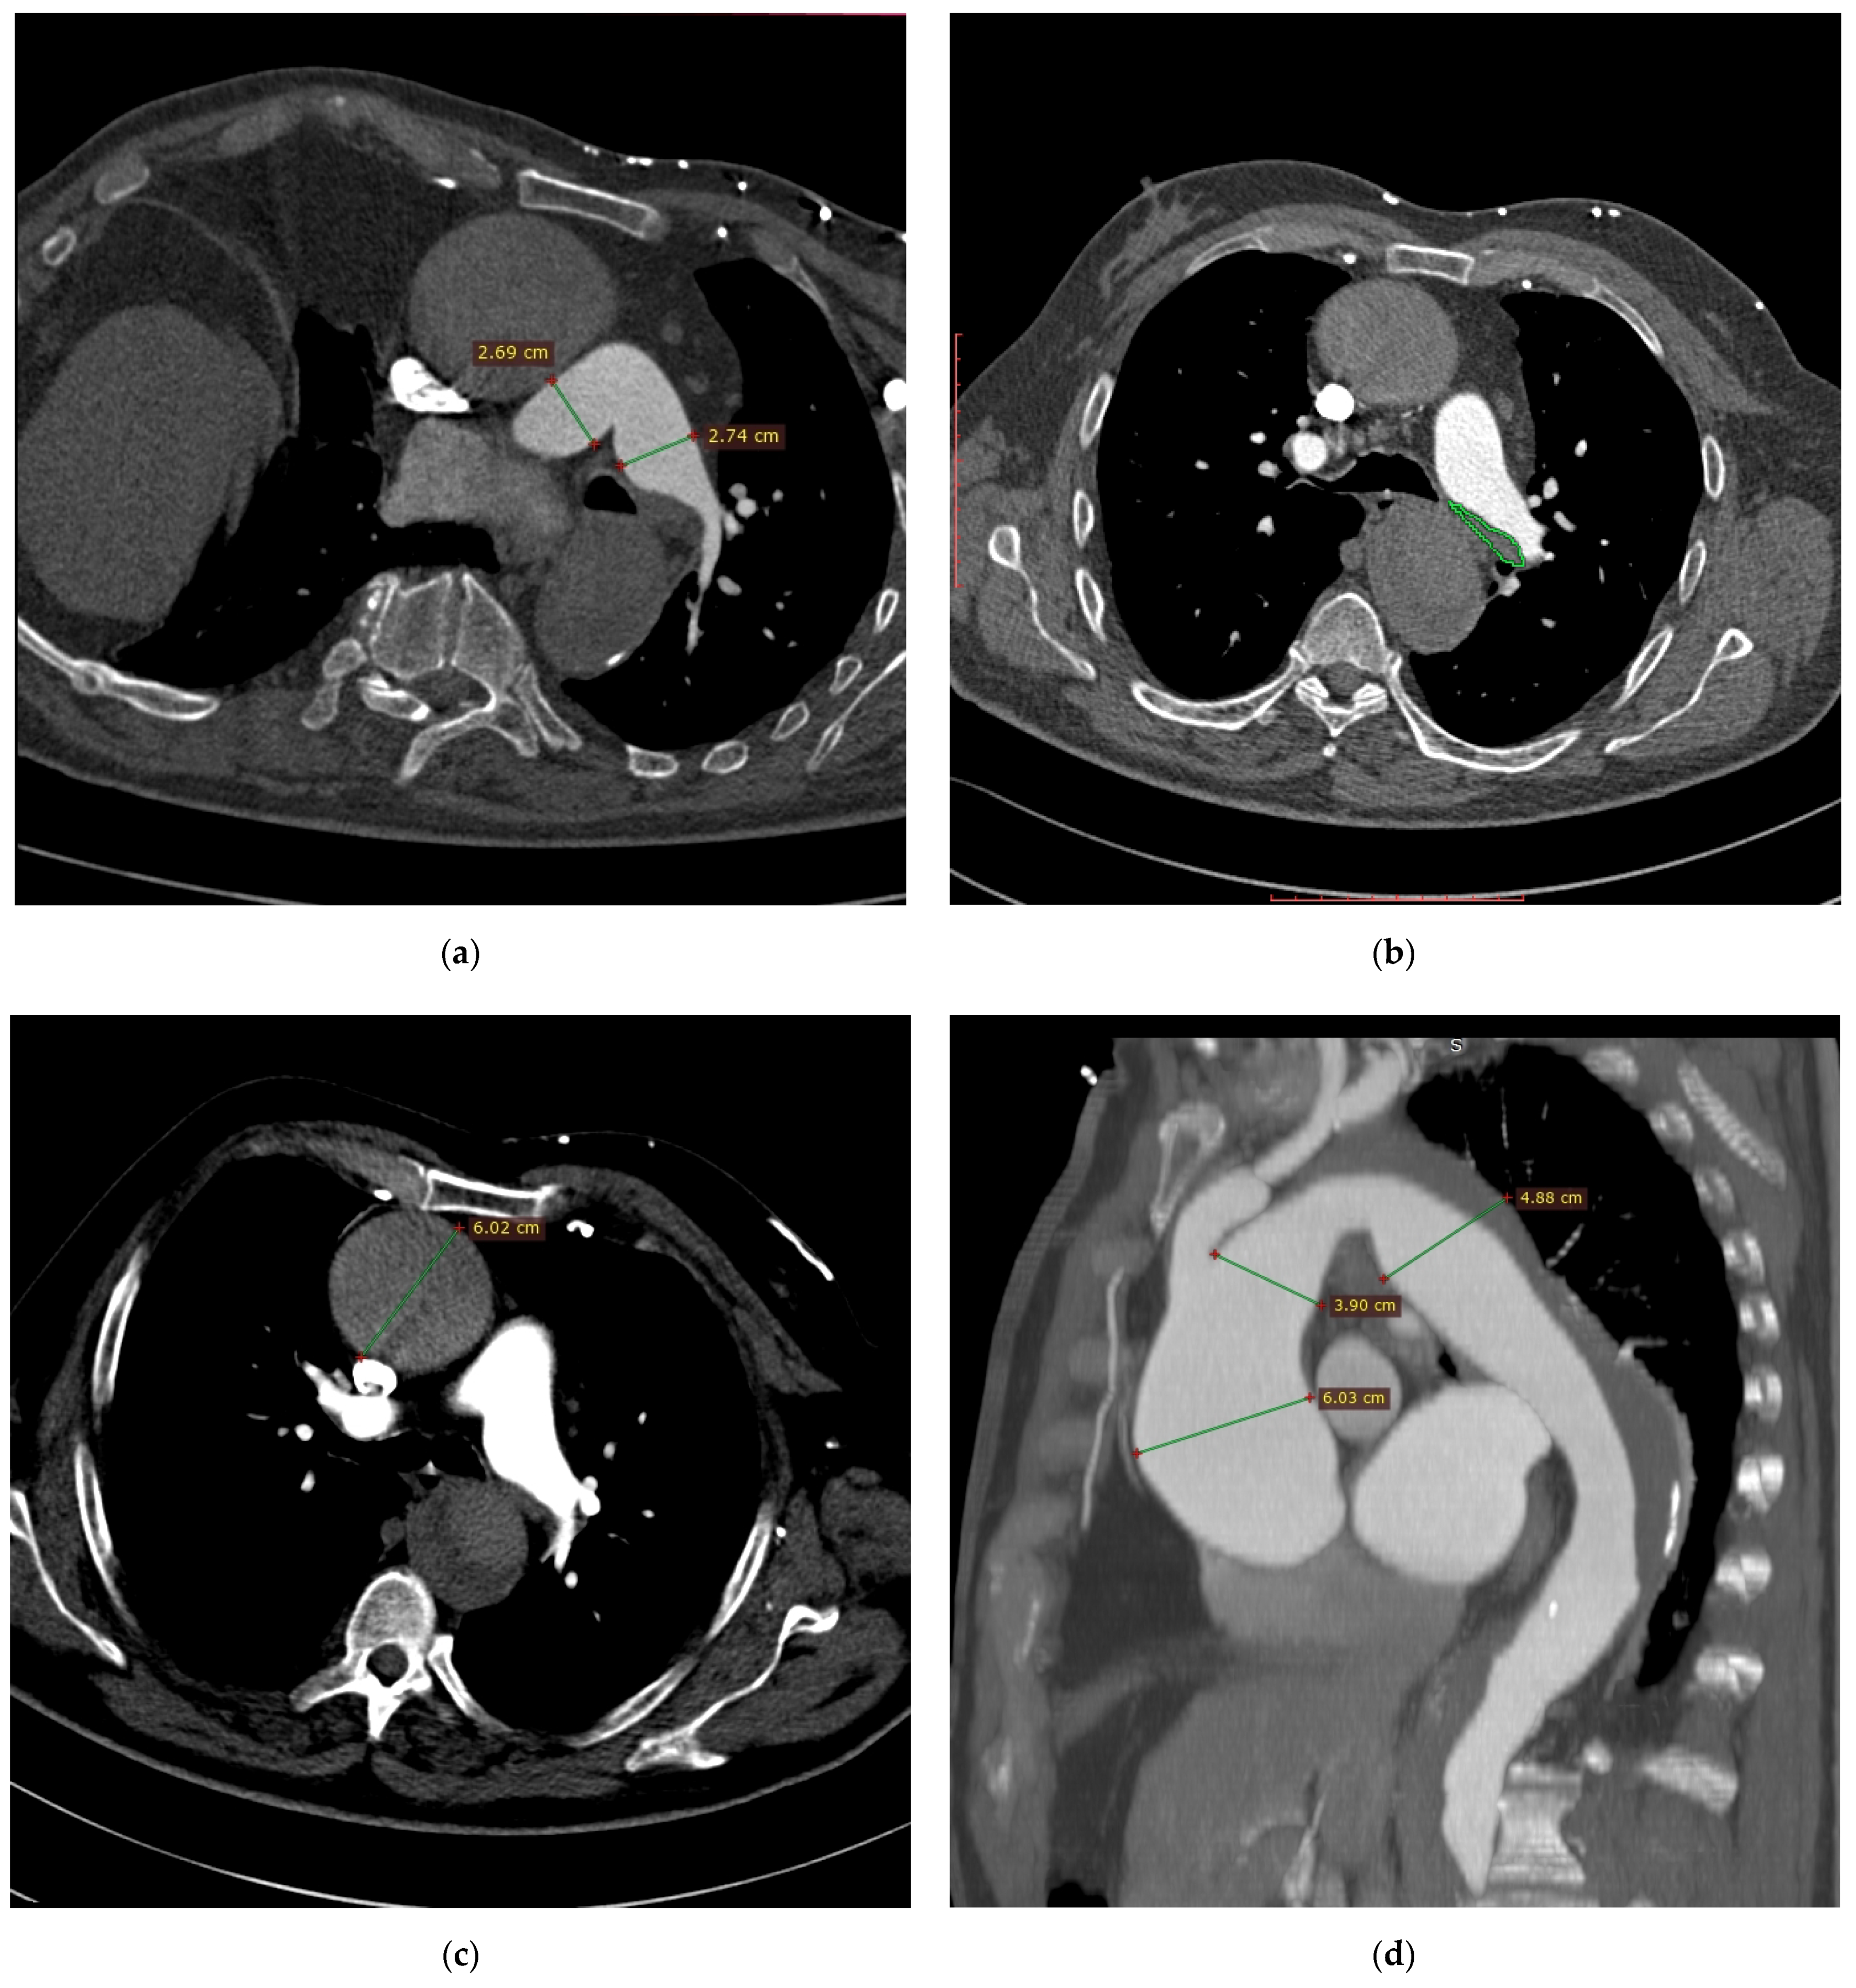

Owing to clinically suspected pulmonary embolism (high D-dimer concentration and presence of dyspnea), computed tomography angiography (CTA) of pulmonary arteries was performed. CTA showed dilation of the right and left pulmonary arteries with a borderline width of the pulmonary trunk (pulmonary trunk diameter about 34 mm, right pulmonary artery diameter about 27 mm, left pulmonary artery diameter about 27 mm) (Figure 1a). Distal section of the left pulmonary artery revealed a parietal irregular filling defect suggesting presence of embolic material (Figure 1b). No other embolic filling defects of arterial vessels were found. The right ventricle was normal-sized (right to left ventricular diameter ratio was 0.62); no angiographic signs of right heart failure were observed (no signs of contrast reflux into inferior vena cava (IVC)). Based on this CTA, diagnosis of pulmonary embolism was suggested. Additionally, CTA showed aortic dilation to about 6.0 cm in the ascending section and non-uniform aortic density suggesting acute aortic syndrome (Figure 1c).

Figure 1.

Computed tomography angiography images: (a) dilation of the right and left pulmonary arteries with a borderline width of the pulmonary trunk; (b) left pulmonary artery filling defect suggesting presence of embolic material; (c) non-uniform aortic density suggesting acute aortic syndrome; (d) aneurysm of the ascending aorta, aortic arch and proximal part of the descending aorta; (e) aortic aneurysm with massive parietal thrombi/aortic aneurysm with chronic dissection and clotting of the supposedly dissected canal; (f) angular (Gothic) aortic arch; (g) stenosis of the proximal section of the superior mesenteric artery; (h) occlusion of the proximal section of the right superficial femoral artery; (i) filling defects in the veins of the right iliac axis that is most probably a thrombotic material.